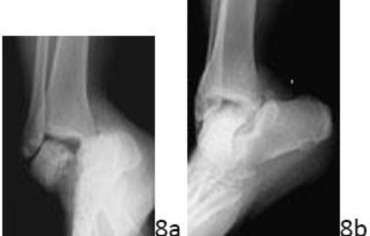

6. # 8a 8b A 35-year-old woman is involved in a head-on collision while driving. Initial radiographs are shown in Figures 8a and 8b. Injury to what vessel increases the risk for osteonecrosis of the injured bone?

DISCUSSION: The patient has a Hawkins type III talar neck fracture-dislocation with a risk of osteonecrosis ranging from 69% to 100%. Anatomic studies have shown that the artery of the tarsal canal supplies the lateral two

thirds of the talar body. The other vessels listed provide no significant contribution to the talus. The Preferred Response to Question # 8 is 4.